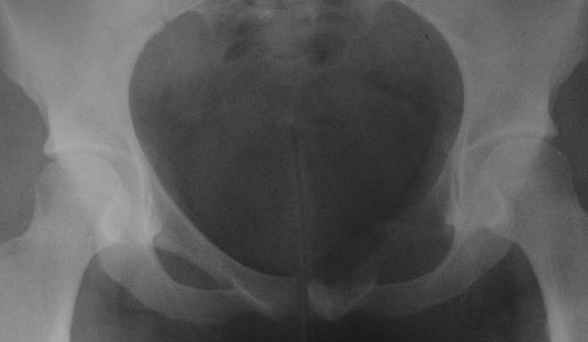

пациентка 20 лет, в сентябре 2005 года почувствовала боли в паху. На снимках заподозрили остеомиелит, лечили антибиотиками без эффекта. К онкологу попала в январе2006. Биопсия в марте 2006 - остеобластокластома. Местные онкологи от операции отказываются.

Вопрос с планом лечения (надо ли замещать деффект и чем) и где оперироваться (опыт подобных операций).В приложении рентгенограммы в динамике (2005 сентябрь, декабрь, 2006 апрель).